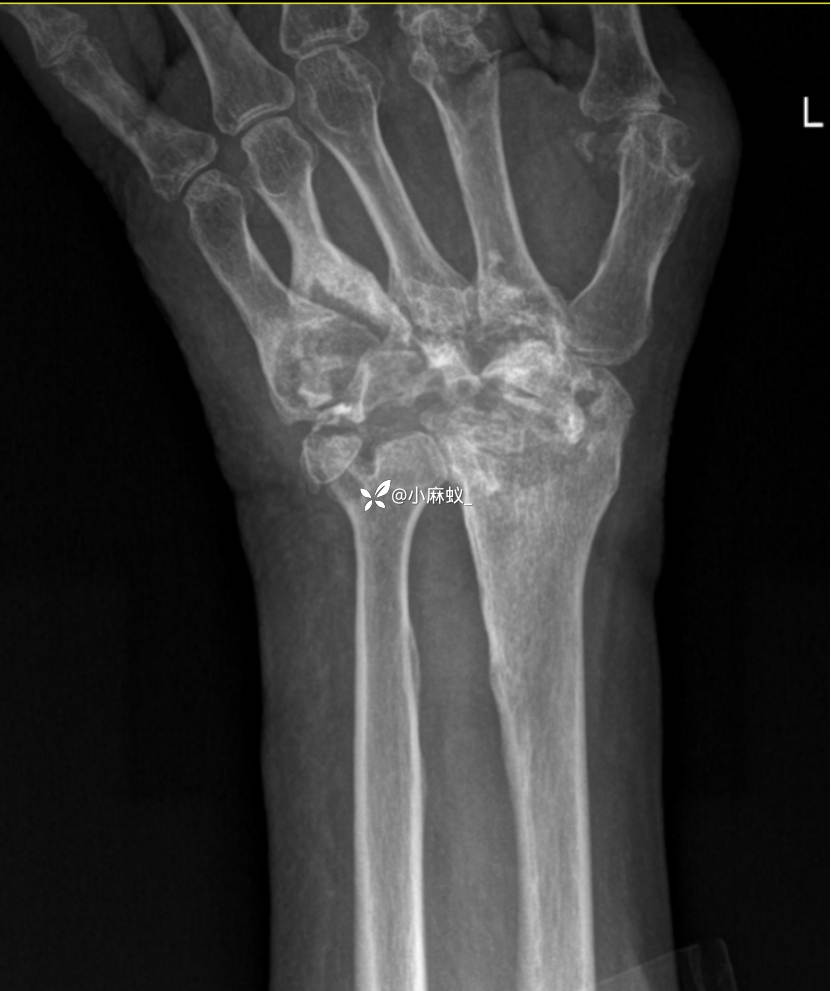

x线检查如下